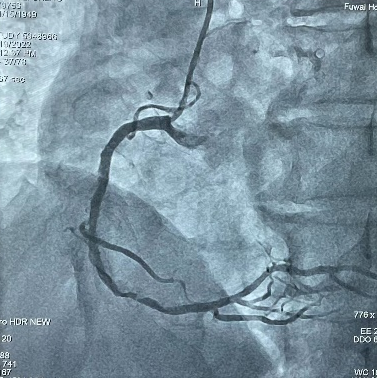

患者为73岁男性,自述间断胸闷已9年有余,近半年胸闷症状复发;经冠脉造影显示,患者右冠状动脉远段有明显狭窄,狭窄率90%,靶血管严重钙化,病变长度目测40mm,参考血管直径为3mm,未见夹层产生,TIMI血流3级,在心脏搏动和不搏动时皆可见清晰高密度影。

在局部麻醉下,经右侧远端桡动脉入路,首先对靶血管进行球囊预扩,然后术者先将2.75*12mm冲击波冠脉球囊送至靶血管近端,并在4atm低压扩张后启动脉冲放电,持续一个治疗周期;然后更换3.0*12mm冲击波冠脉球囊,再次送至靶血管远端,再次进行一个治疗周期的脉冲放电。整个治疗过程总计进行了2个放电治疗周期(总计20次脉冲),钙化斑块被安全地“压裂“,靶血管管腔获得良好,植入串联双支架后经冠脉造影检查显示,支架贴壁良好,未见夹层与血栓,目测残余狭窄0%。